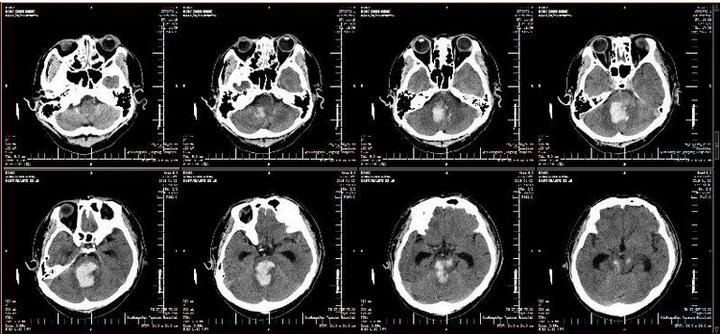

患者48岁,男性,突发昏迷,呼之不应,遂就诊于某医院,急诊头颅CT显示:脑干出血,不除外小脑、第四脑室内出血。入重症医学科治疗,给予降血压、止血、降颅压、营养脑细胞及维持电解质平衡等治疗,病情无好转,出现发热,给予气管插管接呼吸机辅助呼吸,病情危重,患者家属焦急万分,先后咨询多家医院,得到的答复全部都是“手术治疗没有任何意义”。后患者家属带头颅CT片来到秦皇岛军工医院咨询,神经外科主任进行紧急会诊。患者家属得知军工医院神经外科曾治愈多位脑干出血患者,听取医生的会诊意见后,积极要求在军工医院进行手术治疗。

2019年1月2日,军工医院副院长于笑鹏协调急诊科、重症医学科、神经外科、手术室麻醉科做好转接手术患者相关准备工作,紧急召集120急救人员与该医院沟通,将患者接到重症医学科进行术前准备。患者来院后复查头CT显示:脑干内血肿量较前明显增多,出现梗阻性脑积水征象。在院领导的关注下,神经外科医生团队经过两个多小时的精湛手术,患者生命体征平稳。复查头CT显示:脑干内血肿清除彻底,脑积水解除,转回军工医院重症医学科继续治疗。术后6小时,患者自主呼吸恢复,有吞咽动作,格拉斯评分由入院前3分转为5分,各种刺激检测均有反应。

术前ct片